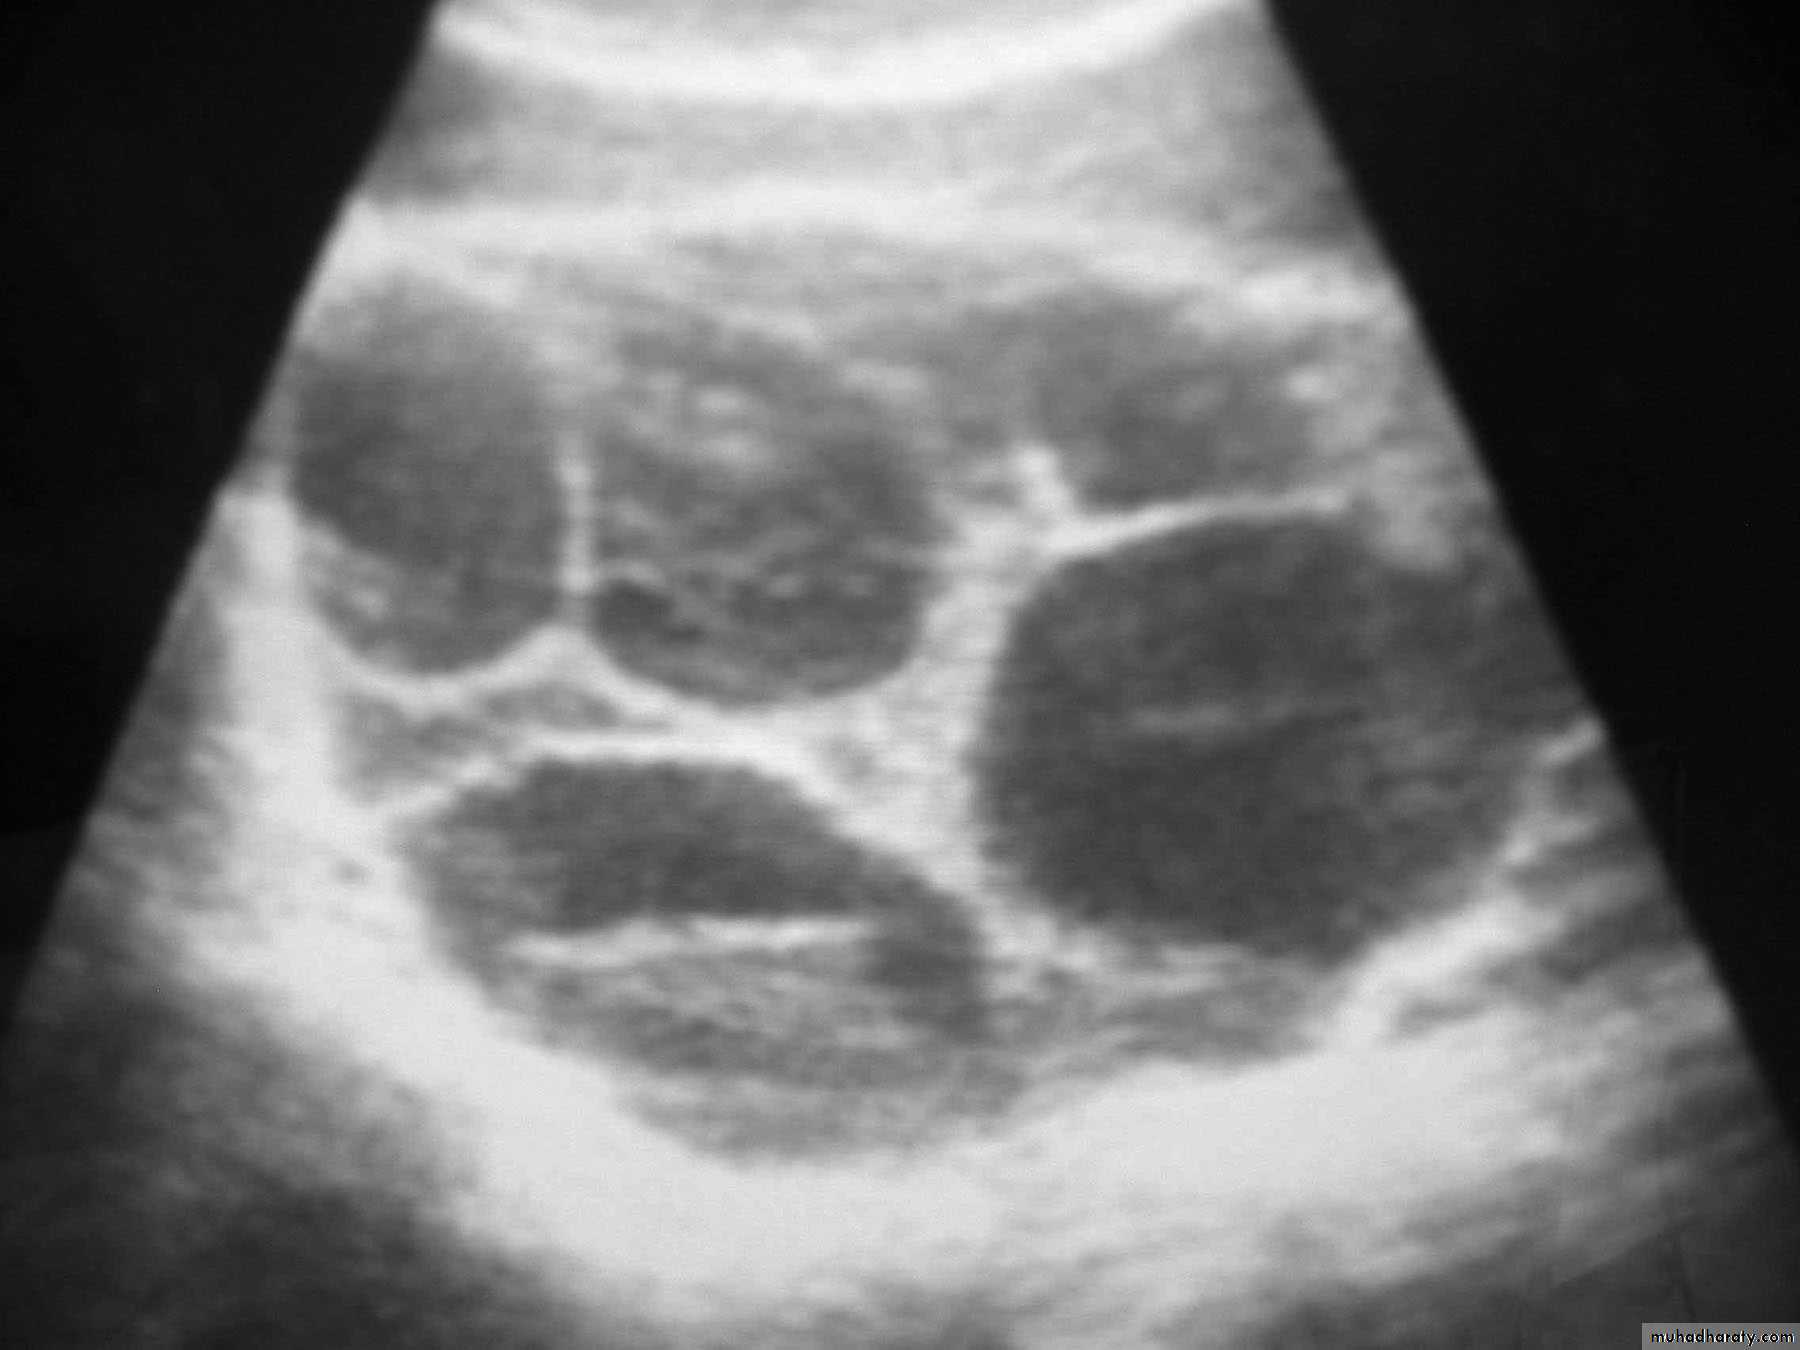

ultrasound:a. which confirm diagnosis of mole as show snowstorm appearance (uterine cavity filled with multiple sonolucent area of varying size and shape).

b. absence of fetus.

Theca Lutein cyst of ovary.